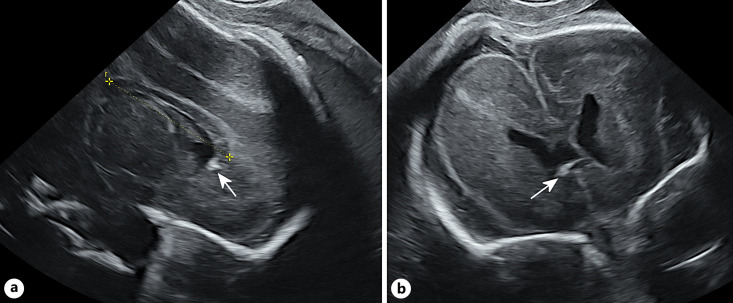

Results: Seventy-two patients were included in our cohort. In 76% infection occurred in the 1st T or periconceptional. In 12 patients, the exact time of infection was inconclusive, including two cases of secondary infection. In 34.7%, a callosal anomaly was observed and it was never isolated. CNS abnormalities included: periventricular hyperechogenicity (PVHE) 55.5%, calcifications 52%, ventriculomegaly 33%, periventricular pseudocysts 31.4%, occipital cysts 22.2%, echogenic ganglionic eminence 30.5%, lentostriatal vasculopathy 26.4%, sulcation abnormalities 22.2%, cerebellar findings 18% and HC below -2 SD 18%. In 19 cases, the CC was short with calcifications in four. In one case, the insult was severe and in another the CC was absent. The most common association with CC insult was PVHE (56%) and calcifications (52%).

Abstract Image